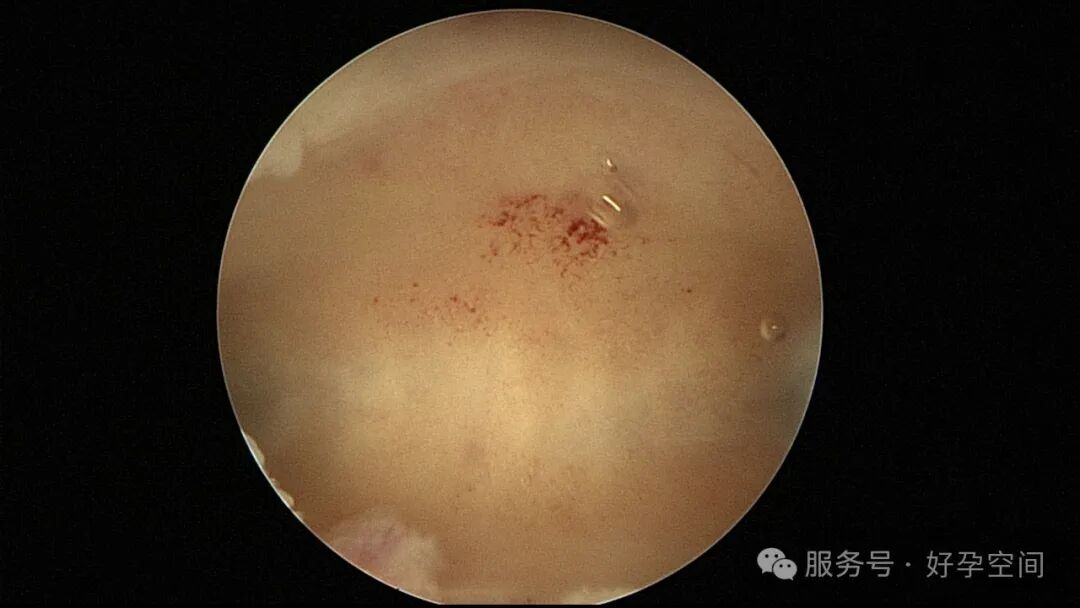

输卵管吻合术后妊娠,稽留流产,清宫术后宫腔粘连,宫腔镜单极电针分粘

分粘后宫腔镜二探,残留少许膜性粘连,镜鞘分粘

试管前宫腔镜检查